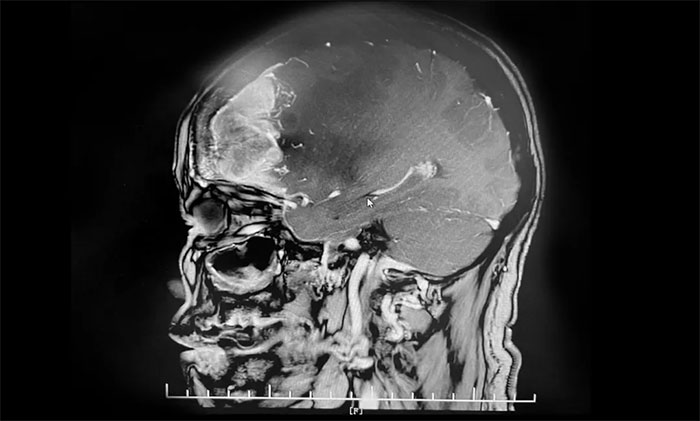

入院后,于耀宇主任为章女士完善检查。头颅MRI增强示:右侧额叶不规则团块状异常信号影,边界不清,最大直径约5.6cm,大小与鸭蛋相仿。病灶周边有大片水肿信号影;邻近大脑脚、胼胝体及双侧侧脑室受压、变形;中线结构左偏。

▲ 肿瘤大小与鸭蛋相仿